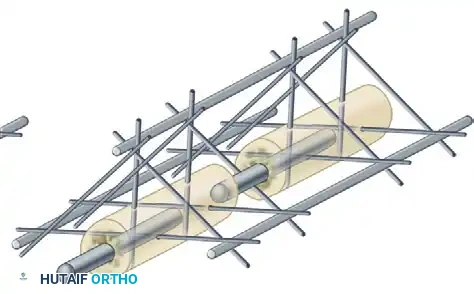

* Multiplanar Constructs: Placing pins in different planes (e.g., a delta frame or biplanar construct) dramatically increases torsional and bending rigidity compared to a uniplanar frame.